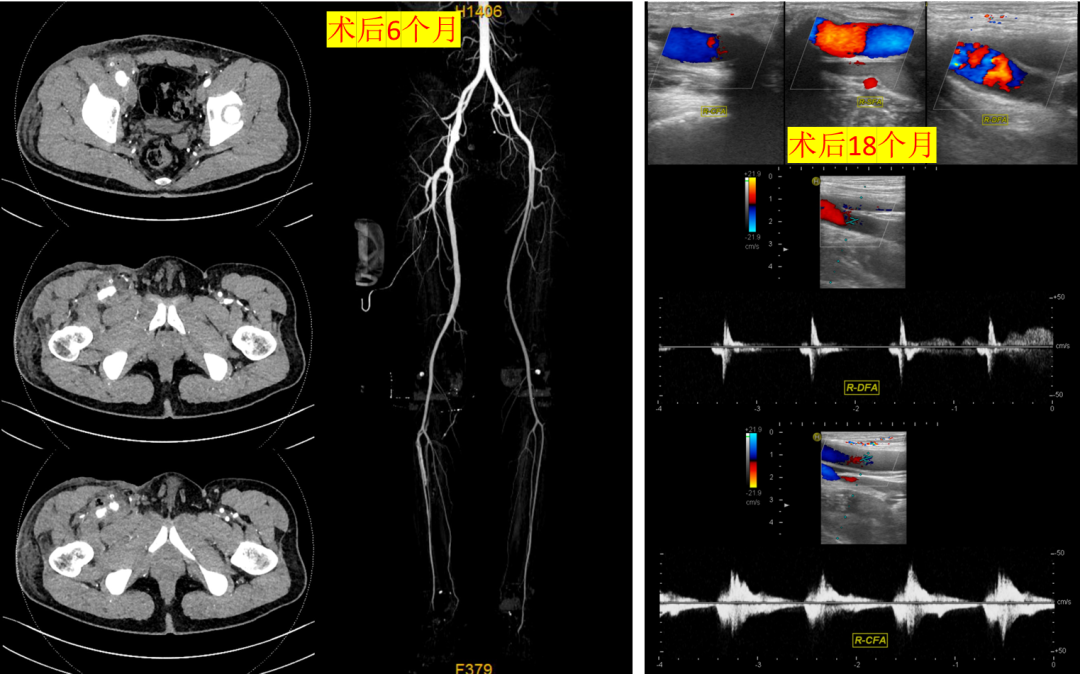

37岁男性,右侧股总动脉瘤

人工血管重建股深和股浅动脉